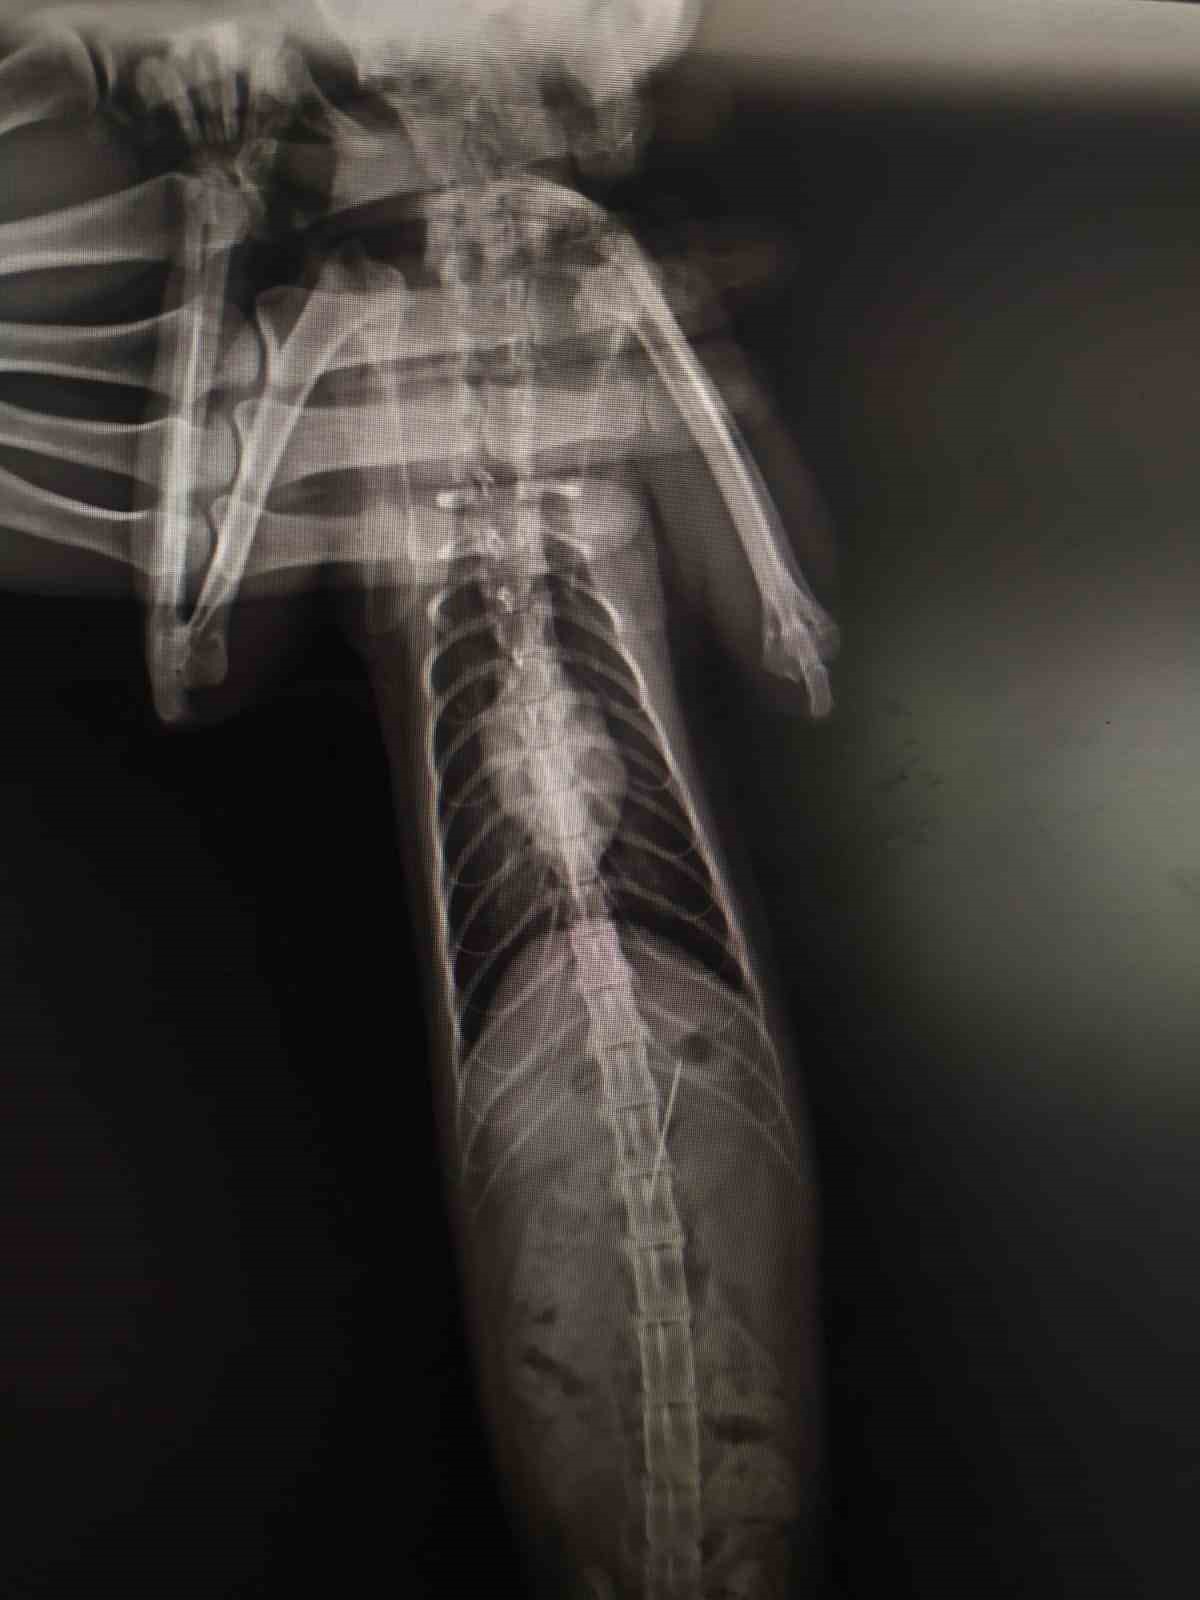

ÇEKİLEN RÖNTGENDE DİKİŞ İĞNESİ YUTTUĞU GÖRÜLDÜ

Bolu'da kedisinin rahatsızlandığını fark eden bir kişi veteriner hekime başvurdu. Edinilen bilgiye göre, özel bir veteriner kliniğinde muayene edilen kedinin röntgeni çekildi. Kedinin midesinde dikiş iğnesi olduğu görüldü. Endoskopiyle dikiş iğnesi kedinin midesinden çıkartıldı. Bir süre veteriner kliniğinde müşahede altında tutulan kedi taburcu edildi.